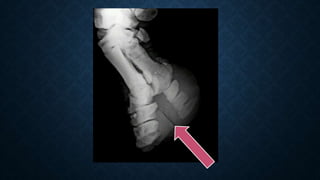

UBERSCHWINGER OR REBOUND EFFECT

• Also called as Halo effect.

• Around the metal or areas where there is a large density

UBERSCHWINGER OR REBOUNDEFFECT • Also called as Halo effect. • Around the metal or areas where there is a large density difference between adjacent objects.